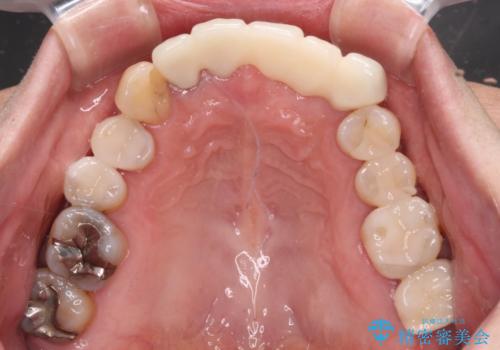

- 前歯の歯肉の腫れを気にして来院された患者様です。

前歯のみならず、奥歯の銀歯や下顎前歯のデコボコなど、色々と気になる部分を治したいとのことでした。

前歯は抜歯が必要であったので、抜歯を行い、その後歯肉移植をおこなった上でオールセラミックブリッジによる補綴治療を行うこととしました。

下顎と上顎臼歯部については矯正治療を行い、奥歯の欠損部位はオールセラミックブリッジを、その他の銀歯はセラミックインレーなどにより治療を行うこととしました。